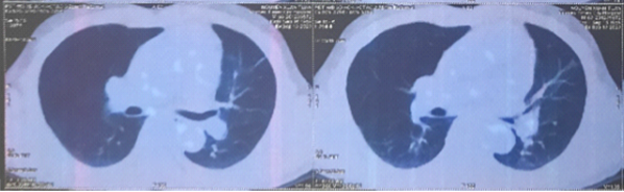

Hình 2: Vài nốt đặc nhu mô phổi 2 bên, kích thước lớn nhất 5x6mm

Hình 3: Nhu mô hạ phân thùy VII có vài khối, nốt kích thước lớn nhất 33x26mm giảm tỷ trọng trước tiêm, ngấm thuốc thì động mạch (vòng tròn đỏ), thải thuốc thì tĩnh mạch cửa (vòng tròn).

Cắt lớp vi tính ổ bụng có tiêm thuốc cản quang:

Hình 4: Theo dõi di căn hạch rốn gan (vòng tròn trắng).